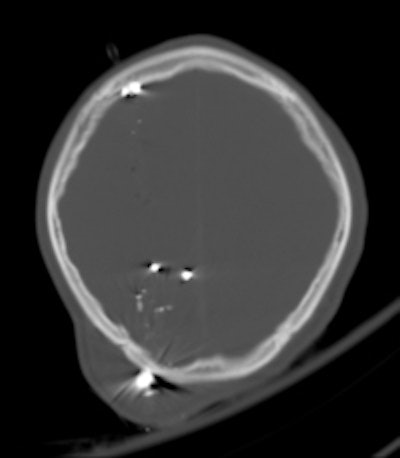

A 30-year-old male with a gunshot wound to the head. Left: Brain window axial CT image demonstrates a significant soft-tissue swelling and underlying fracture at the entry site of the projectile. The course of the bullet is seen by a linear hemorrhage through the right cerebral hemisphere. There is loss of the grey-white differentiation in keeping with a diffuse hypoxic injury. Right: The fragmentation and scatter of the low-velocity projectile is best seen on CT bone windows. All images courtesy of Dr. Andrew Shawyer.Doctors involved in the care of these patients need to understand the patterns and mechanisms of the injuries, he explained. To accurately interpret images of gunshot wounds, a basic knowledge of ballistics is important, especially the factors affecting the extent and type of tissue damage. Such knowledge is useful not only for evaluating acute injuries but also for determining the path of the missile, awareness of missile fragmentation, and embolization, thus contributing to the overall clinical, and often the forensic, picture.